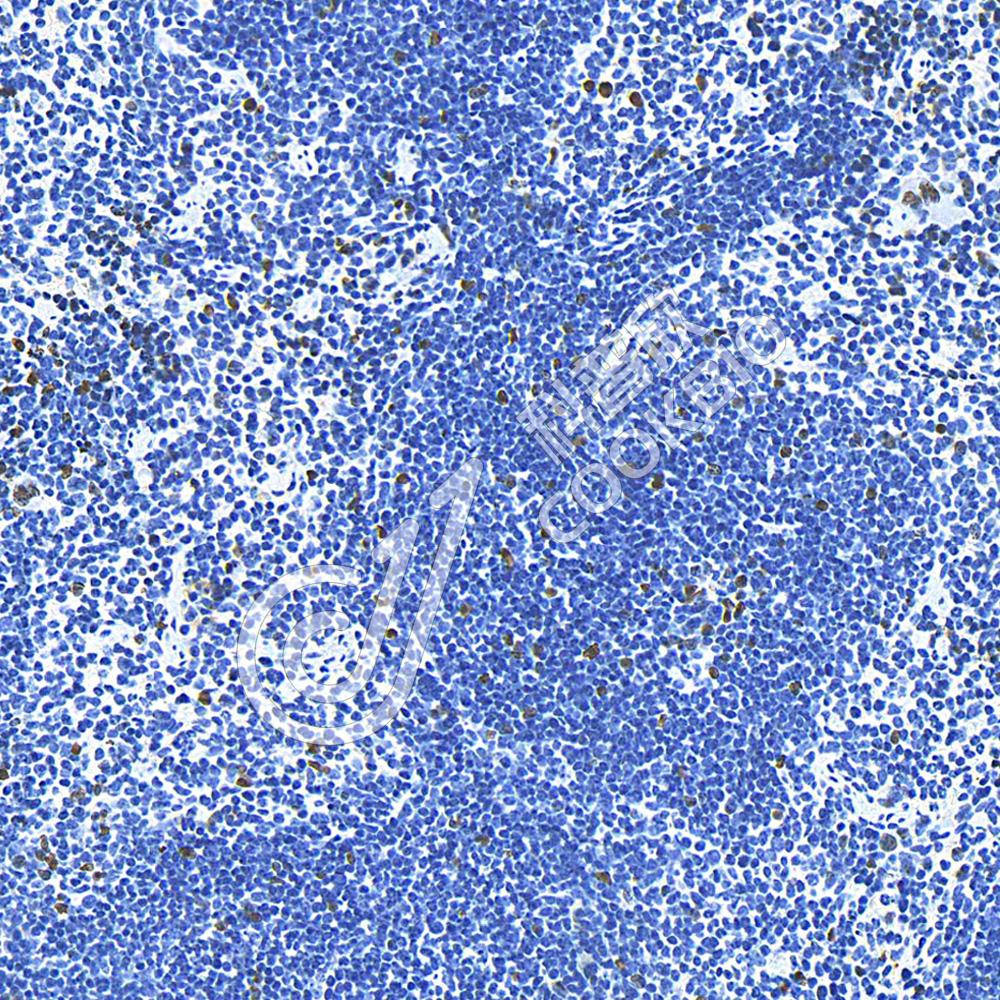

IHC检测BrdU蛋白(货号 K545153).

样品: 小鼠脾, 4%多聚甲醛 (货号KSG1101) 固定12-24小时.

抗原修复: 柠檬酸抗原修复液(干粉, pH 6.0) (KSG1201), 98℃, 20分钟.

—抗: 1: 800稀释, 4℃ 孵育过夜.

二抗: S-vision免疫组化多聚二抗(山羊抗小鼠), 即用型(货号KB3903), 室温孵育20分钟.